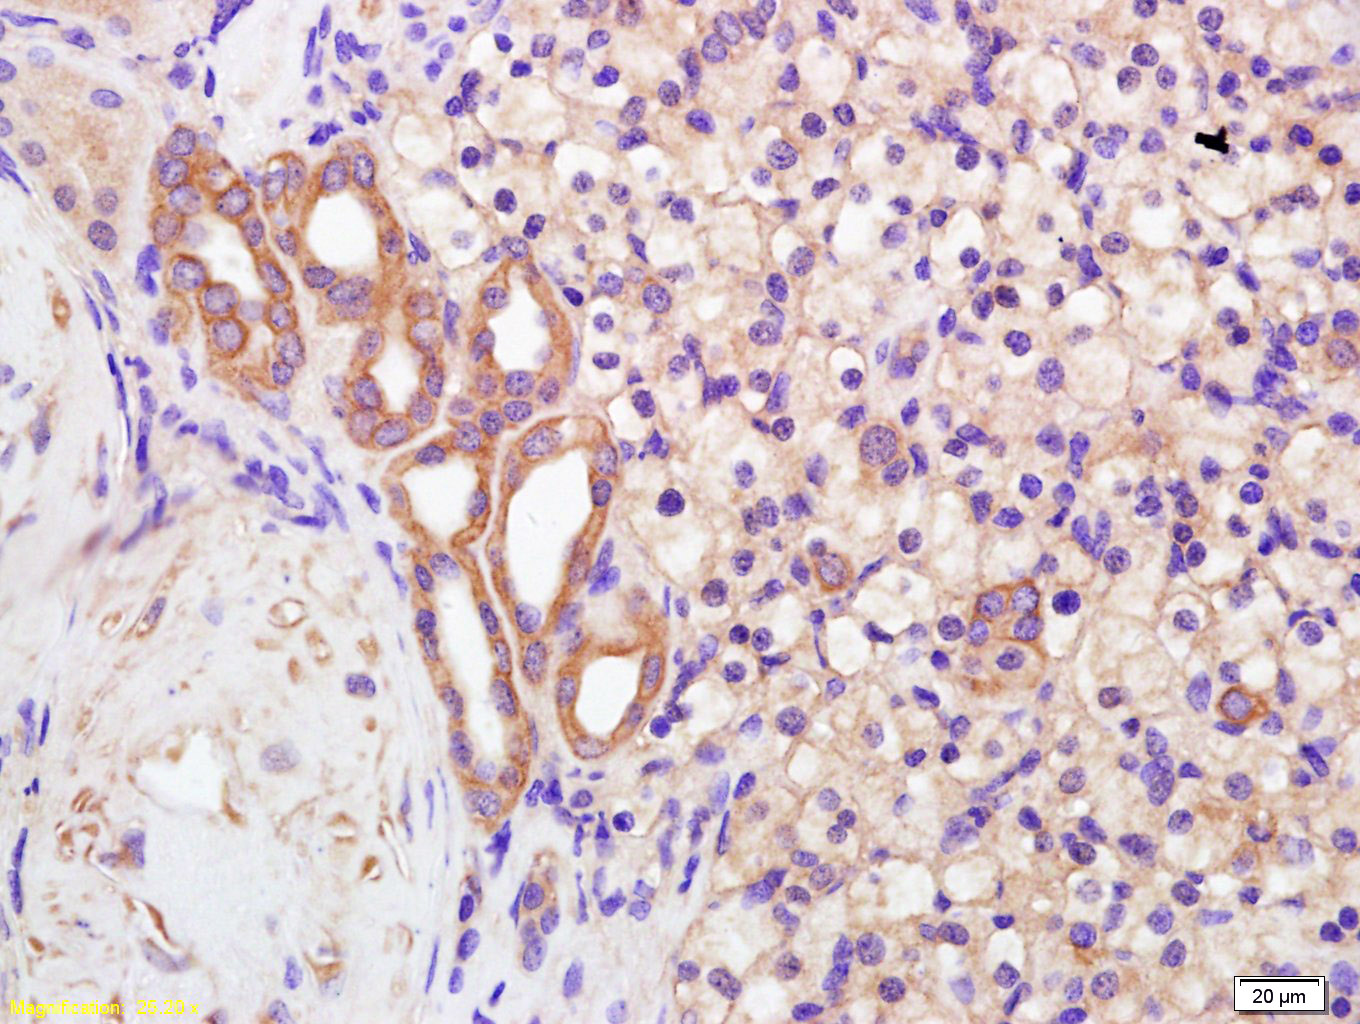

Tissue/cell: human kidney carcinoma; 4% Paraformaldehyde-fixed and paraffin-embedded; Antigen retrieval: citrate buffer ( 0.01M, pH 6.0 ), Boiling bathing for 15min; Block endogenous peroxidase by 3% Hydrogen peroxide for 30min; Blocking buffer (normal goat serum,C-0005) at 37℃ for 20 min; Incubation: Anti-Polycystin 2 Polyclonal Antibody, Unconjugated(bs-2158R) 1:200, overnight at 4°C, followed by conjugation to the secondary antibody(SP-0023) and DAB(C-0010) staining